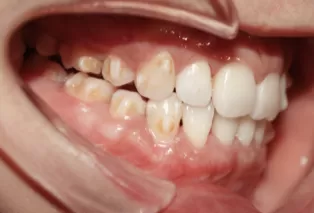

Intraoral photos